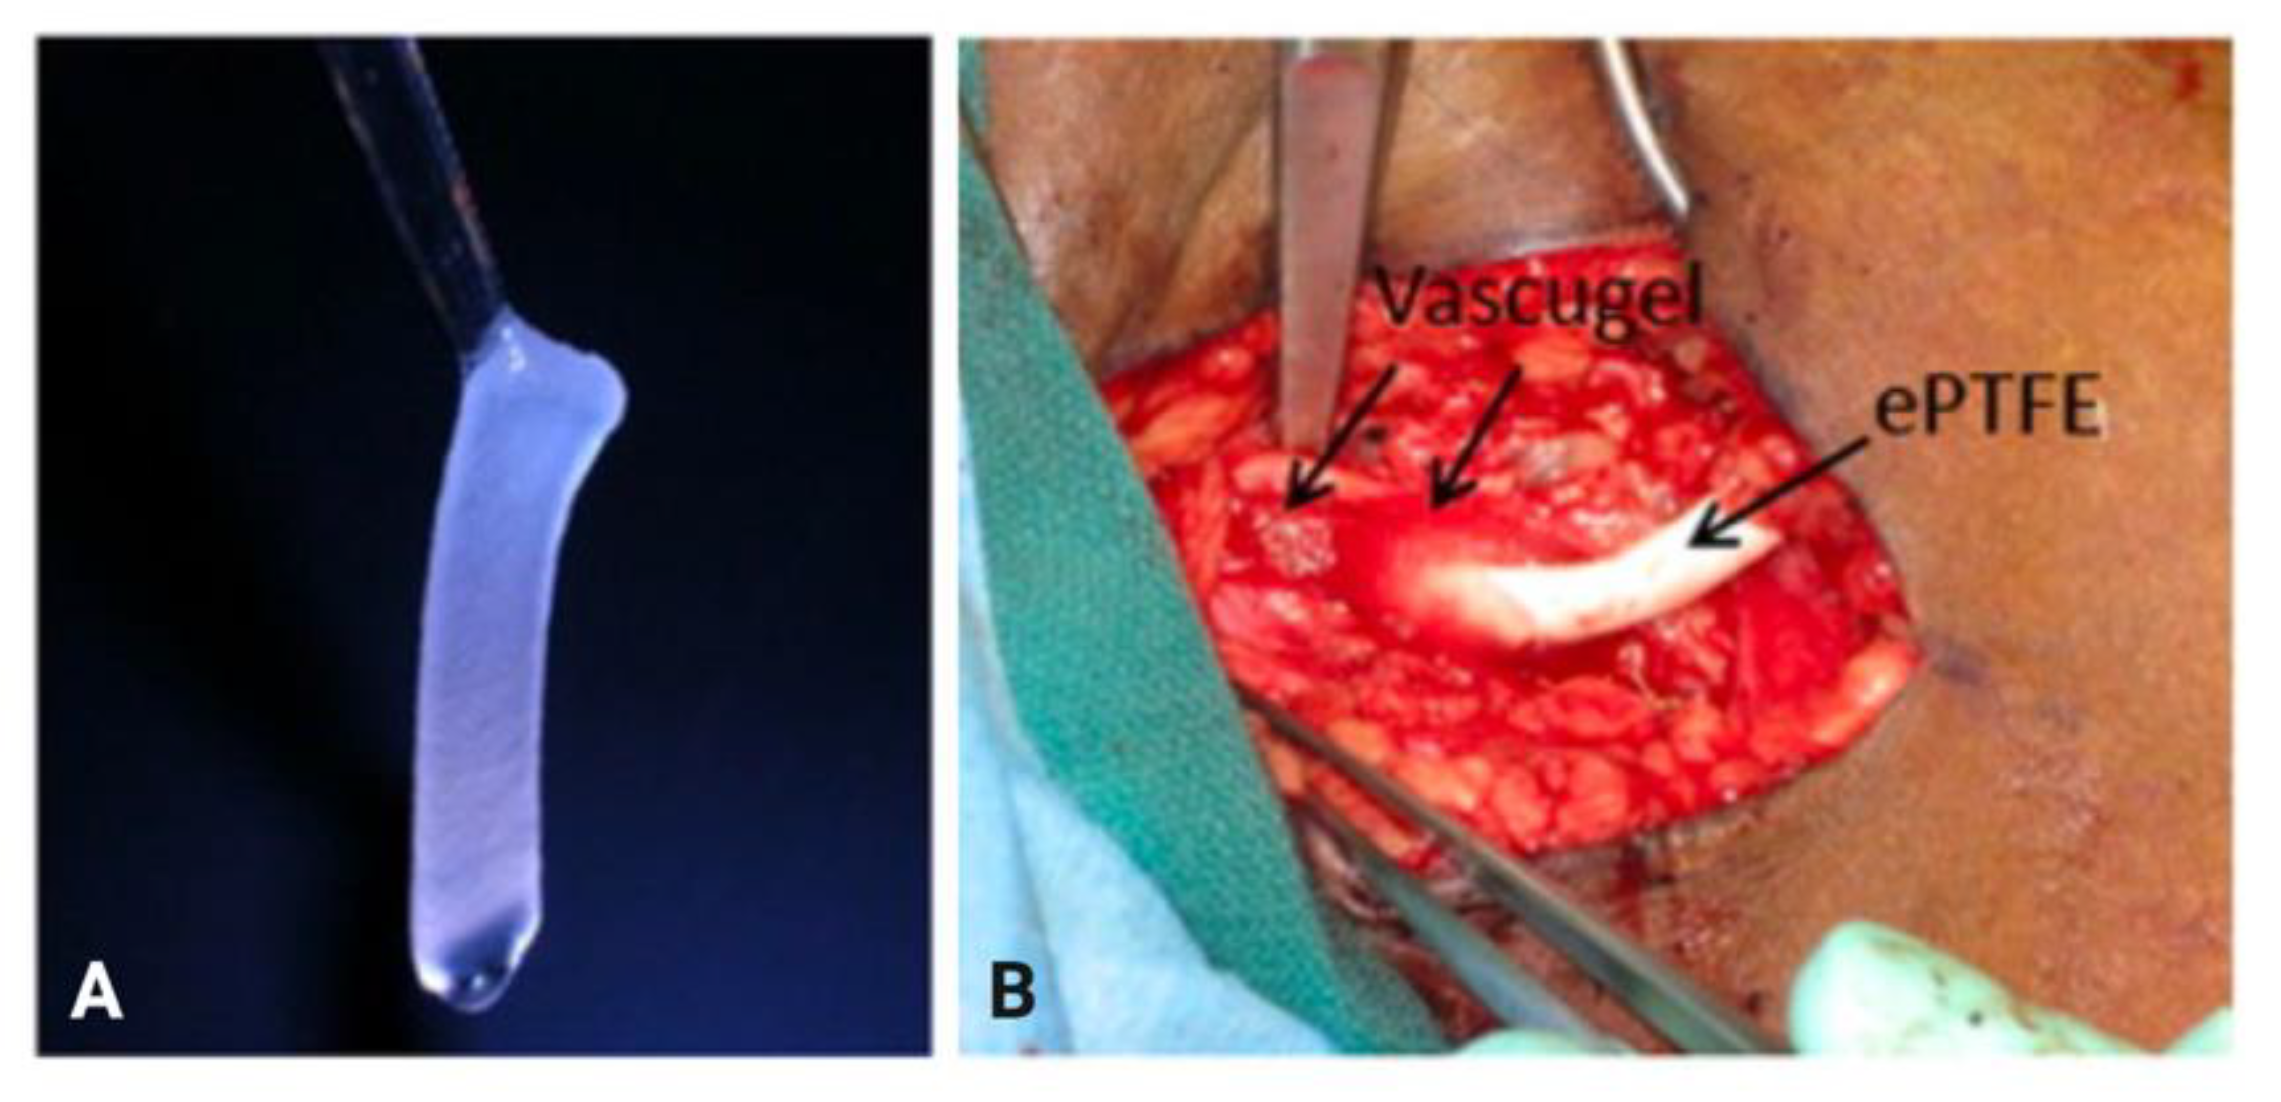

- Conte, M.S.; Nugent, H.M.; Gaccione, P.; Guleria, I.; Roy-Chaudhury, P.; Lawson, J.H. Multicenter Phase I/II Trial of the Safety of Allogeneic Endothelial Cell Implants after the Creation of Arteriovenous Access for Hemodialysis Use: The V-HEALTH Study. J. Vasc. Surg. 2009, 50, 1359–1368. [Google Scholar] [CrossRef][Green Version]